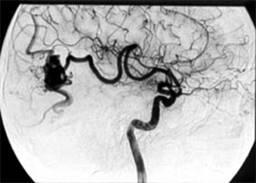

4. Суперселективная эмболизация или тромбирование АВМ. (N-бутилцианоакрилат (Hystoacryl) + жирорастворимое контрастное вещество). Рис.1.

Рис.1

Ангиограмма больной с аневризмой левой височной доли до операции.

Контрольная ангиограмма той же больной после эмболизации